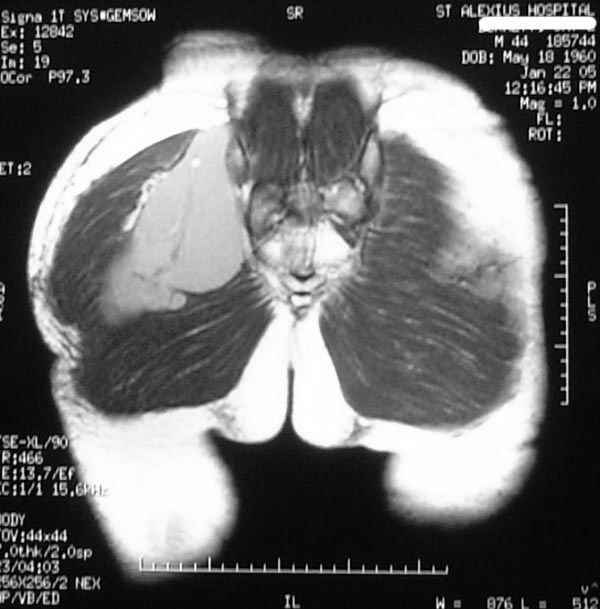

Уважаемые коллеги, Неоднократные пункционные эвакуация (3 раза) крови из ягодичной области, после полученной пройзводственной травмы (более 1.5 мес) ударом в ягодицу тяжелым, около полутонны предметом.

Рентгенограмма без особенностей, несмещенные переломы лонной и седалищных костей таза. Последная пункция 10 дней назад 180 мл темной крови, после пункции сделано магнито-резонансные исследование (на снимках), какой диагноз и тактика дальнейшего лечения, какие рекомендации? Джолдас Кульджанов